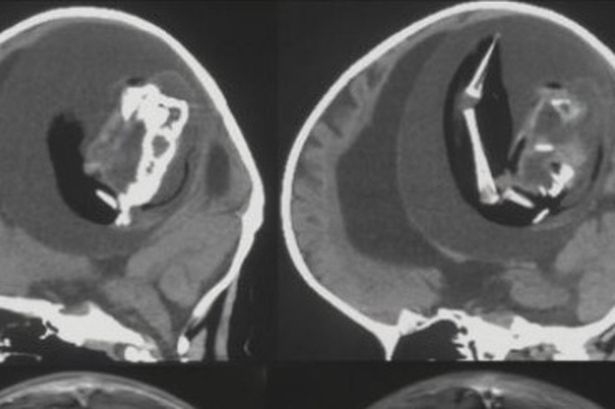

CT scans revealed her unborn sibling was pressed against her brain.

She also had hydrocephalus, the build-up of fluid deep within the brain that can cause an enlarged head, extreme sleepiness, and seizures.

Dr. Zongze Li, a neurologist at Huashan Hospital, Fudan University who treated the girl, said: ‘The intracranial fetus-in-fetu is proposed to arise from unseparated blastocysts.

‘The conjoined parts develop into the forebrain of the host fetus and envelop the other embryo during neural plate folding.’